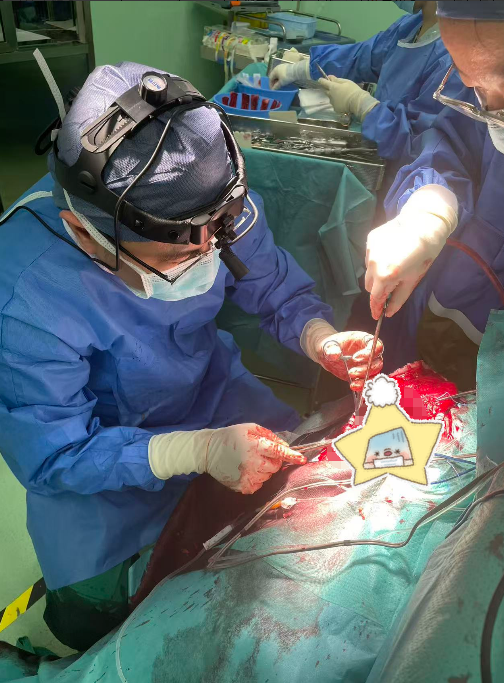

无影灯下,主刀医生赵坚柱凭借丰富的经验和精湛的技术,小心翼翼地清除血肿,细致处理骨折部位,精准进行止血操作。麻醉团队全程严密监控患者生命体征,手术护士默契配合,确保手术顺利进行。经过五个多小时的紧张奋战,手术团队成功清除了患者左侧及右侧的颅内血肿,妥善处理了颅骨骨折,彻底解除了脑组织受压状况。整个手术过程中,团队成员沉着冷静,配合默契,以专业素养牢牢守住了生命的最后防线。